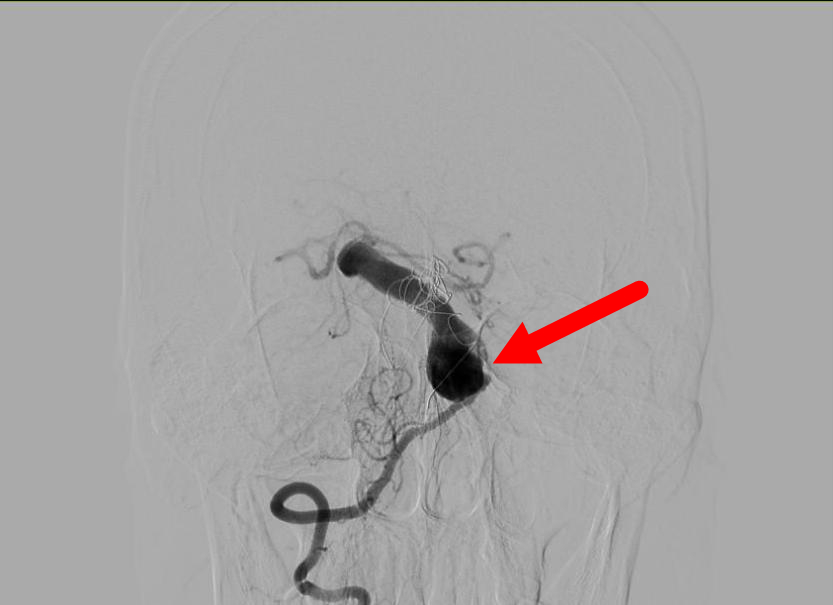

当检查画面映入眼帘时,惊呆了在场的所有人,第一次手术填塞的金属弹簧圈,已经因为动脉瘤的扩张,变成一堆杂乱无章的铁丝线排列在李先生的脑子里。造影后的图像更是让人咋舌:一个 10*30 mm 巨大的夹层动脉瘤盘踞在脑干的前方,而且基底动脉异常的扩张。

基底动脉是生命的主干道,掌管着呼吸、心跳、意识等核心功能,比喻为「生命禁区」毫不为过。并且,夹层动脉瘤意味着血管壁已经撕裂,比普通动脉瘤更脆弱。再加上,既往的治疗可能还会阻碍正常的器械通过。这是「难上+难上+难」。处理李先生复发的动脉瘤犹如在「神经核弹」上作业,稍有不慎,将会导致严重后果。考虑到此夹层动脉瘤破裂风险之高,已经没有再等待随诊观察的时间,家属同意尽快进行手术。